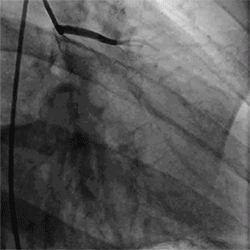

06造影下的心脏